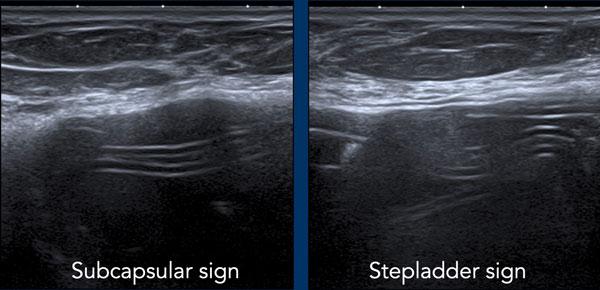

Vỡ túi trong bao xơ (Intracapsular rupture)

Khi vỏ bọc bị vỡ nhưng bao xơ vẫn còn nguyên vẹn, tình trạng này được gọi là vỡ túi trong bao xơ.

Silicone di chuyển vào khoang giữa vỏ bọc và bao xơ, nhưng không di chuyển vào mô vú hoặc ra ngoài.

Các dấu hiệu cần tìm kiếm:

- Dấu hiệu dưới bao xơ (Subcapsular sign): Các đường song song nằm bên trong lòng túi độn ngực, không đi theo phức hợp vỏ bọc-bao xơ bên ngoài.

- Dấu hiệu thang (Stepladder sign): Nhiều lớp đường song song nằm bên trong lòng túi độn.

Dấu hiệu này tương tự dấu hiệu Linguine quan sát được trên MRI. - Xảo ảnh bão tuyết (Snowstorm artefacts) nằm ngoài vỏ bọc

Dấu hiệu thang (Stepladder sign)

Siêu âm có thể phát hiện vỡ túi trong bao xơ bằng cách xác định một chuỗi các đường thẳng hoặc đường cong tăng âm nằm ngang, tương đối song song với nhau, đi ngang qua bên trong lòng túi độn, thường được gọi là “dấu hiệu thang” (stepladder sign).

Điều quan trọng là không được nhầm lẫn dấu hiệu thang với các nếp gấp hướng tâm nổi bật bình thường.